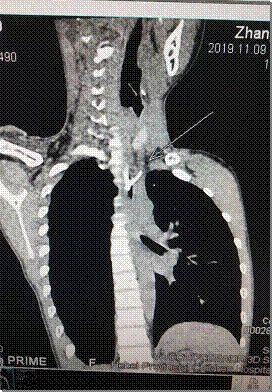

复查胸部高分辨CT后,发现这不是一个普通的食道异物。此异物为分叉的鸡骨,上下长约3.5cm,周围间隙模糊,似可见少量气体影,不排除少量血液渗出,高度怀疑是否出现了食管的穿孔。